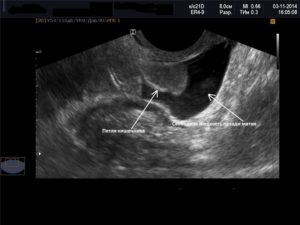

На экране УЗ-сканера жидкостные образования за маткой выглядит черного или темно-серого цвета, чаще имеет форму узкой полоски, если ее количество небольшое.

При большом количестве она растекается между органами и принимает неправильную форму.

Точного количества жидкости за маткой в миллилитрах с помощью этого метода определить невозможно из-за того, что жидкость растекается между складками брюшины и органами и не принимает какой-то строгой формы. Тем не менее для описания количества жидкости на УЗИ в полости малого таза существуют определенные критерии.

Врач измеряет наибольшую длину вертикального уровня жидкости за маткой. Если высота уровня жидкости составляет до 10 мм, то ее количество считается незначительным.